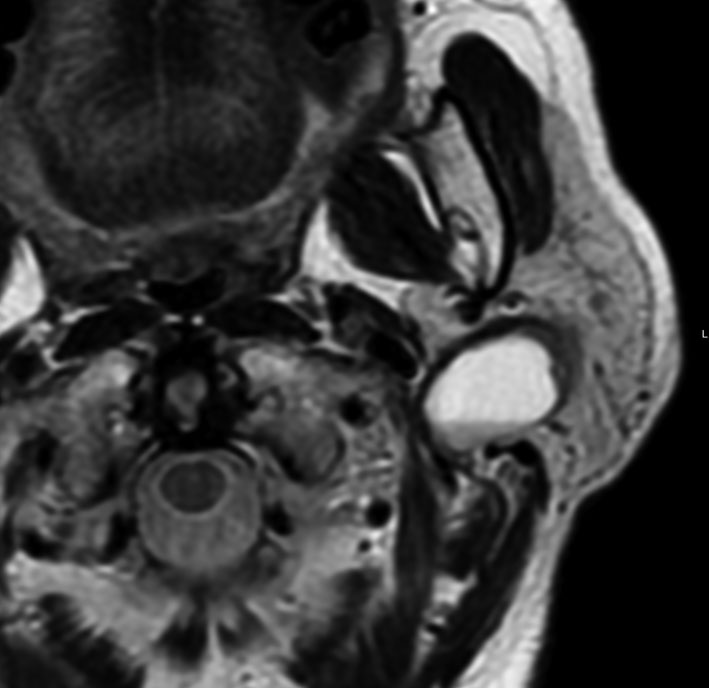

耳下腺内顔面神経鞘腫